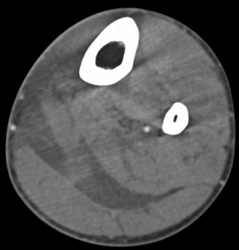

Severe Lymphedema